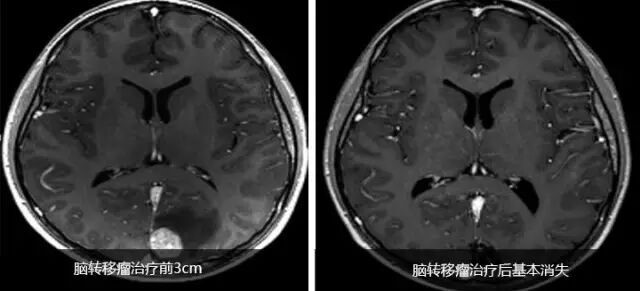

成功案例

患者男性,65岁。2014年10月,患者感到腹部不适、头疼。

检查和诊断结果为

(1)高分化肝细胞癌,大小约10cm,肝硬化明显。

(2)脑转移瘤,左枕叶处有大小约3cm的肿块。

(3)II型糖尿病,需要胰岛素治疗。

(4)慢性肾病;

(5)中度高血压,有心衰病史。

患者处于肝癌晚期,肝癌病灶巨大且有脑转移,国内医疗机构不能实施外科手术治疗。经全球肿瘤医生网请国际癌症专家组远程会诊,患者定于2014年11月10日出国进行EDGE速锋刀无创手术治疗。

半年后,患者身体状态良好,体重明显增加。影像检查报告显示肝脏的巨大肿瘤被彻底清除,脑部肿瘤几乎完全消除,且没有复发。生化检查结果表明肝功能未见异常。